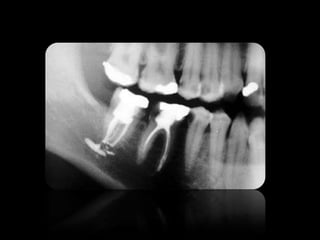

REABSORCIONES ÓSEAS

REABSORCIÓN DENTAL EXTERNA

REABSORCIÓN DENTAL INTERNA